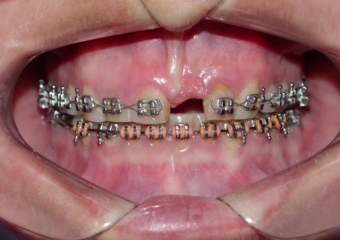

Imagens iniciais observando a ausência do incisivo central superior esquerdo